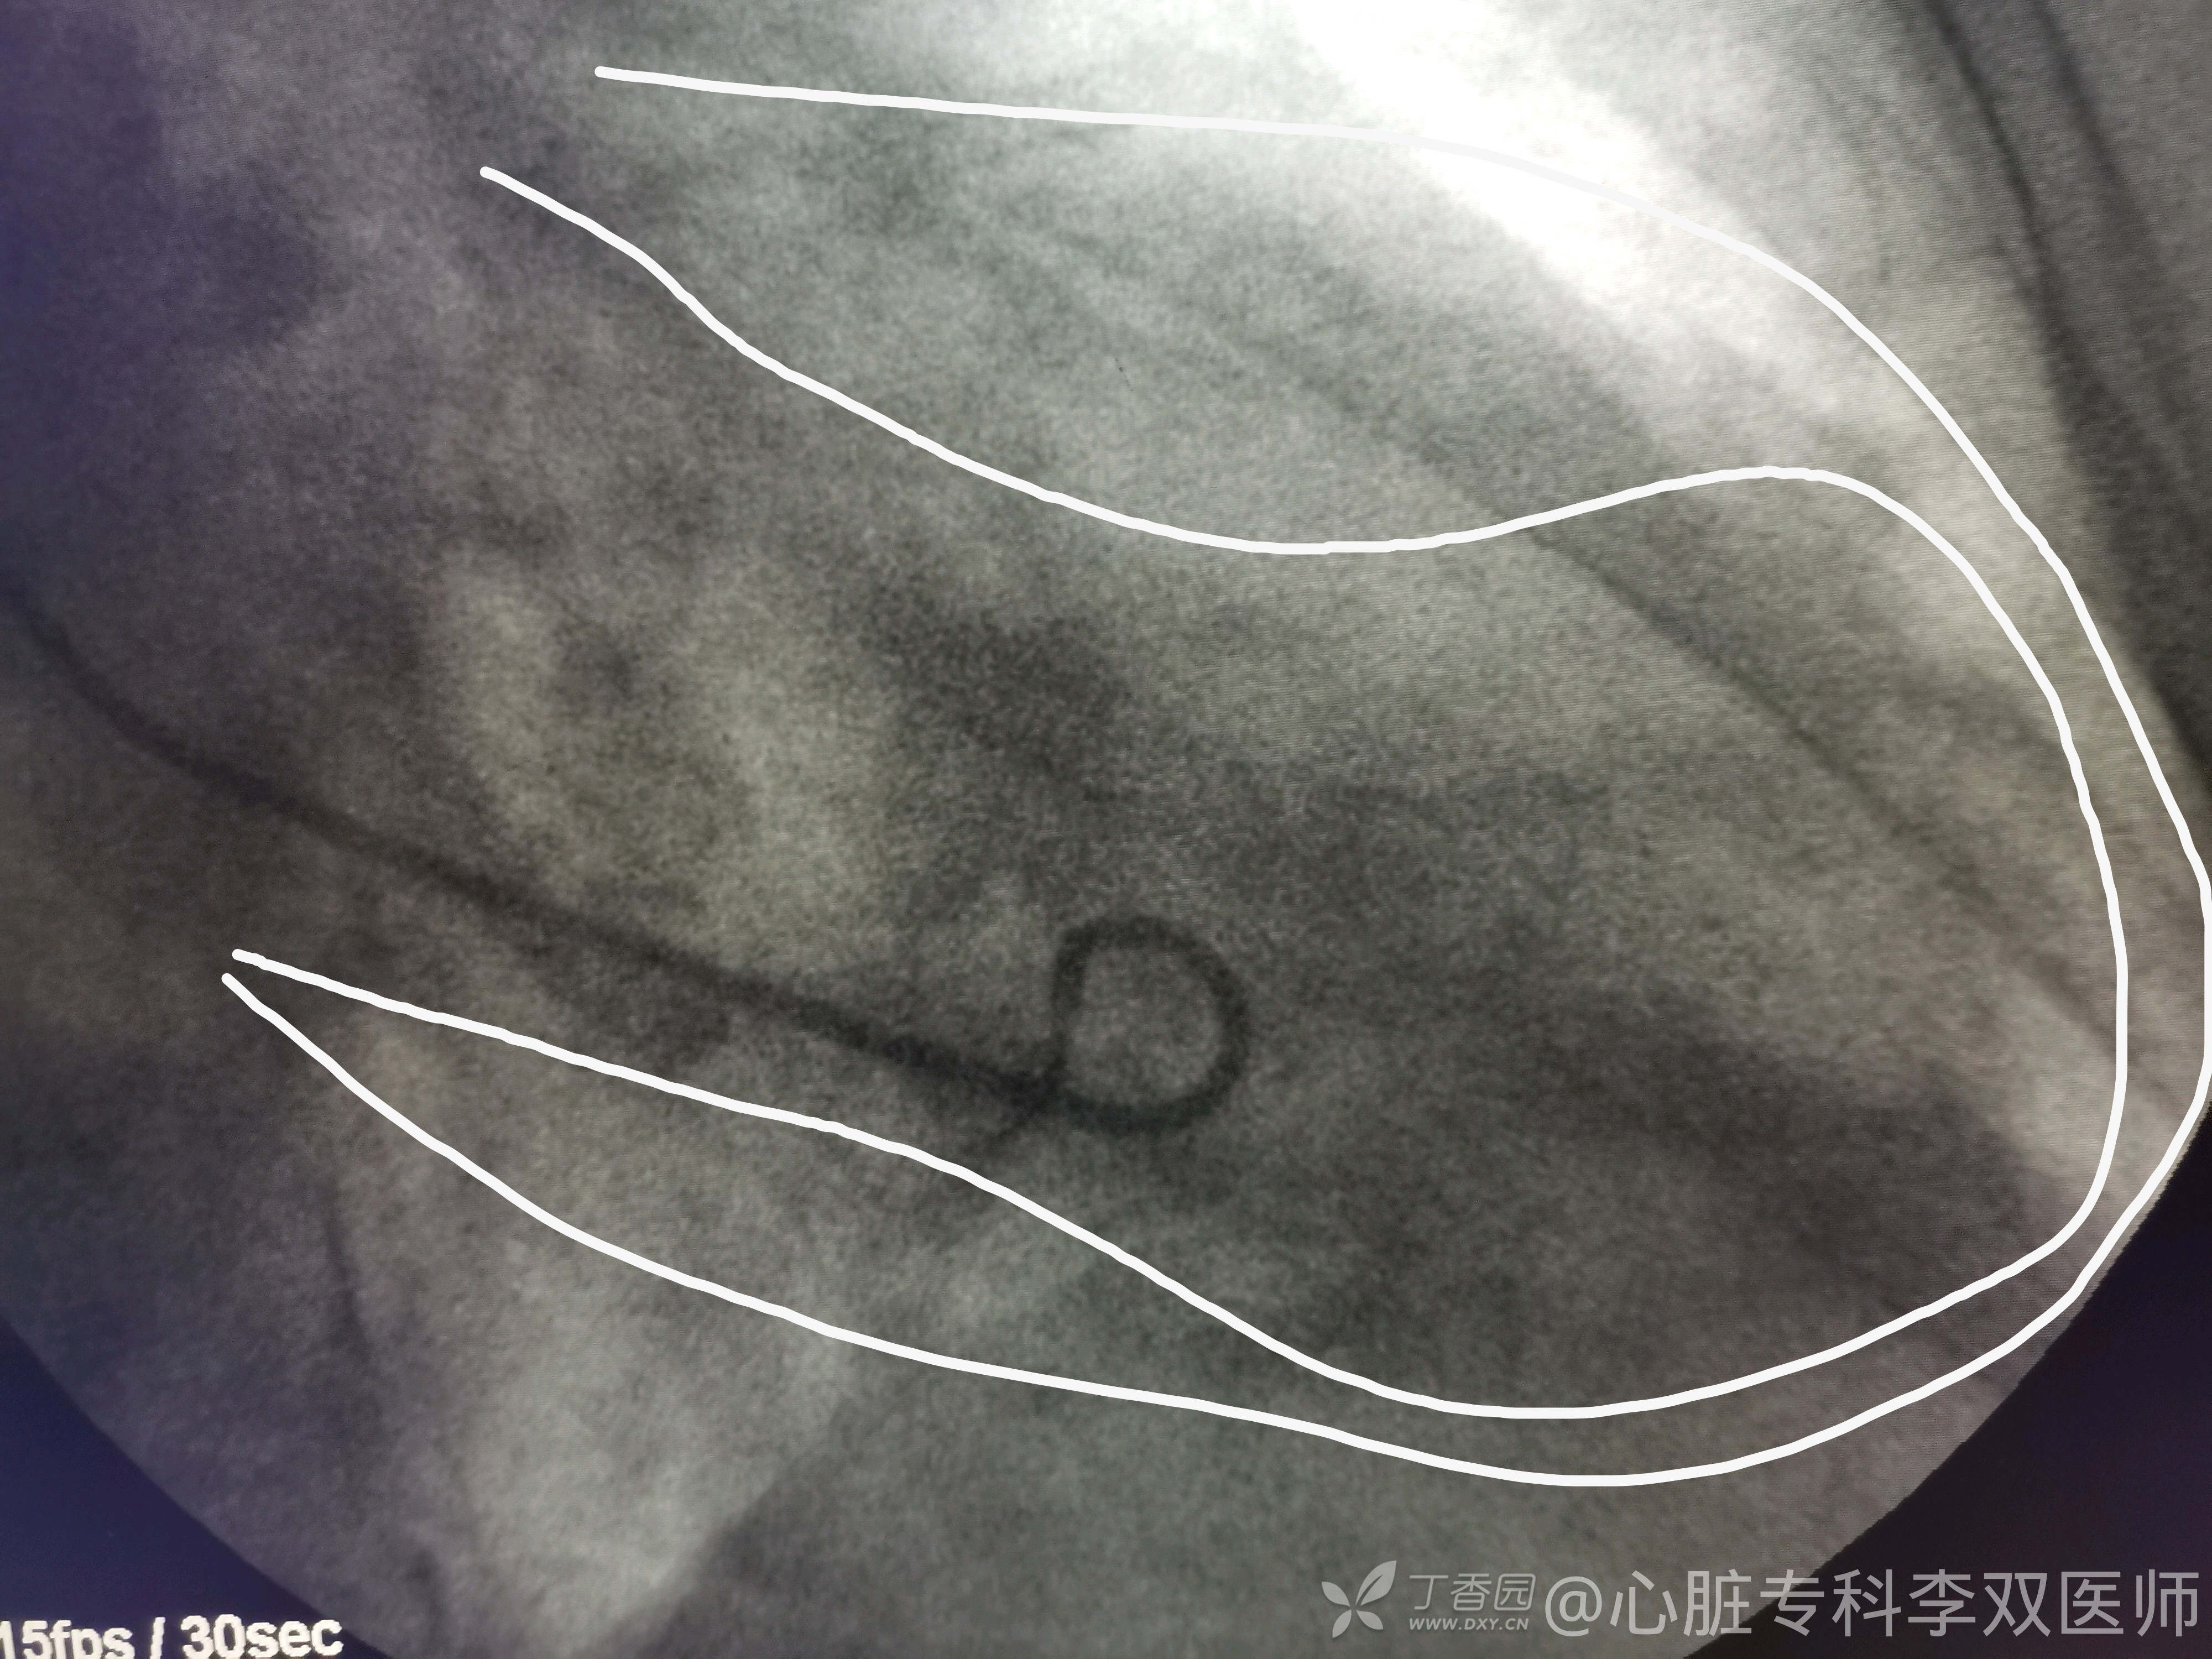

我们会诊考虑确实不能排除心梗,当时做了急诊冠脉造影,不是心梗!(彩超没有报室壁瘤,不过它也排除了血栓,所以才敢打心室造影的)。

心尖部大室壁瘤引起的前壁和侧壁ST抬高,推测患者20年前放支架是急性前壁心梗。